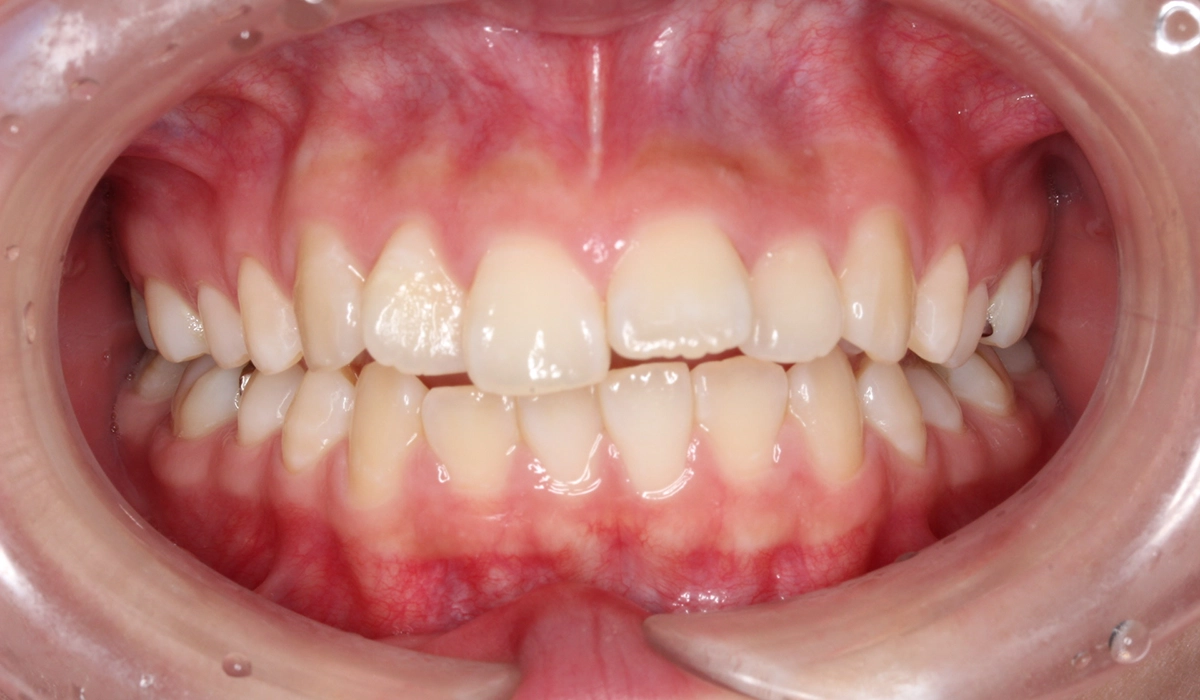

術前:正面

術後:正面